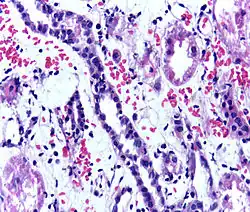

Acute rejection is another possible complication of kidney transplantation; it is graded according to the Banff Classification, which incorporates various serologic, molecular, and histologic markers to determine the severity of the rejection. Acute rejection can be classified as T-cell-mediated, antibody-mediated, or both (mixed rejection). Common causes of acute rejection include inadequate immunosuppression treatment or non-adherence with the immunosuppressive regimen.[79] Clinical acute rejection (seen in approximately 10-15% of kidney transplants within the first year of transplantation) presents as kidney rejection with associated kidney dysfunction.[79] Subclinical rejection (seen in approximately 5-15% of kidney transplants within the first year of transplantation) presents as rejection incidentally seen on biopsy but with normal kidney function.[79] Acute rejection with onset 3 months or later after transplantation is associated with a worse prognosis.[79] Acute rejection with onset less than 1 year after transplantation is usually T cell mediated, whereas onset greater than 1 year after transplantation is associated with a mixed T cell and antibody-mediated inflammation.[79]